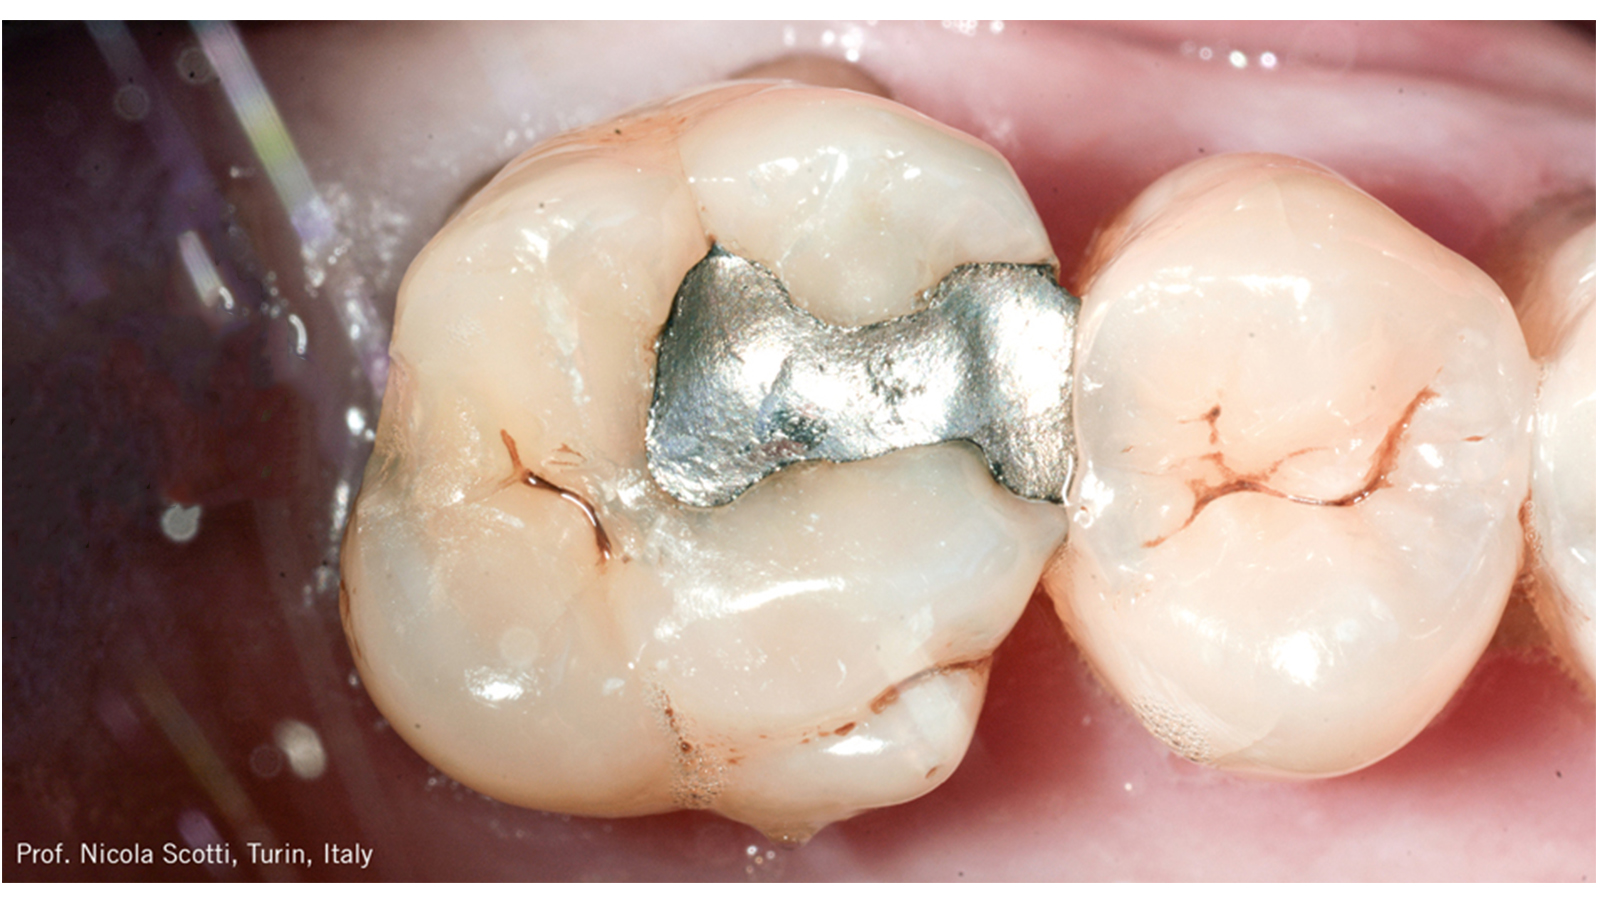

Este caso do Prof. Nicola Scotti (Universidade de Turim, Itália) mostra a eficiência e excelente estética de uma restauração com Charisma Diamond ONE

Cárie secundária na restauração de amálgama do dente 26.

Paciente do sexo masculino, 59 anos, apresentando cárie secundária na restauração de amálgama do dente 26.